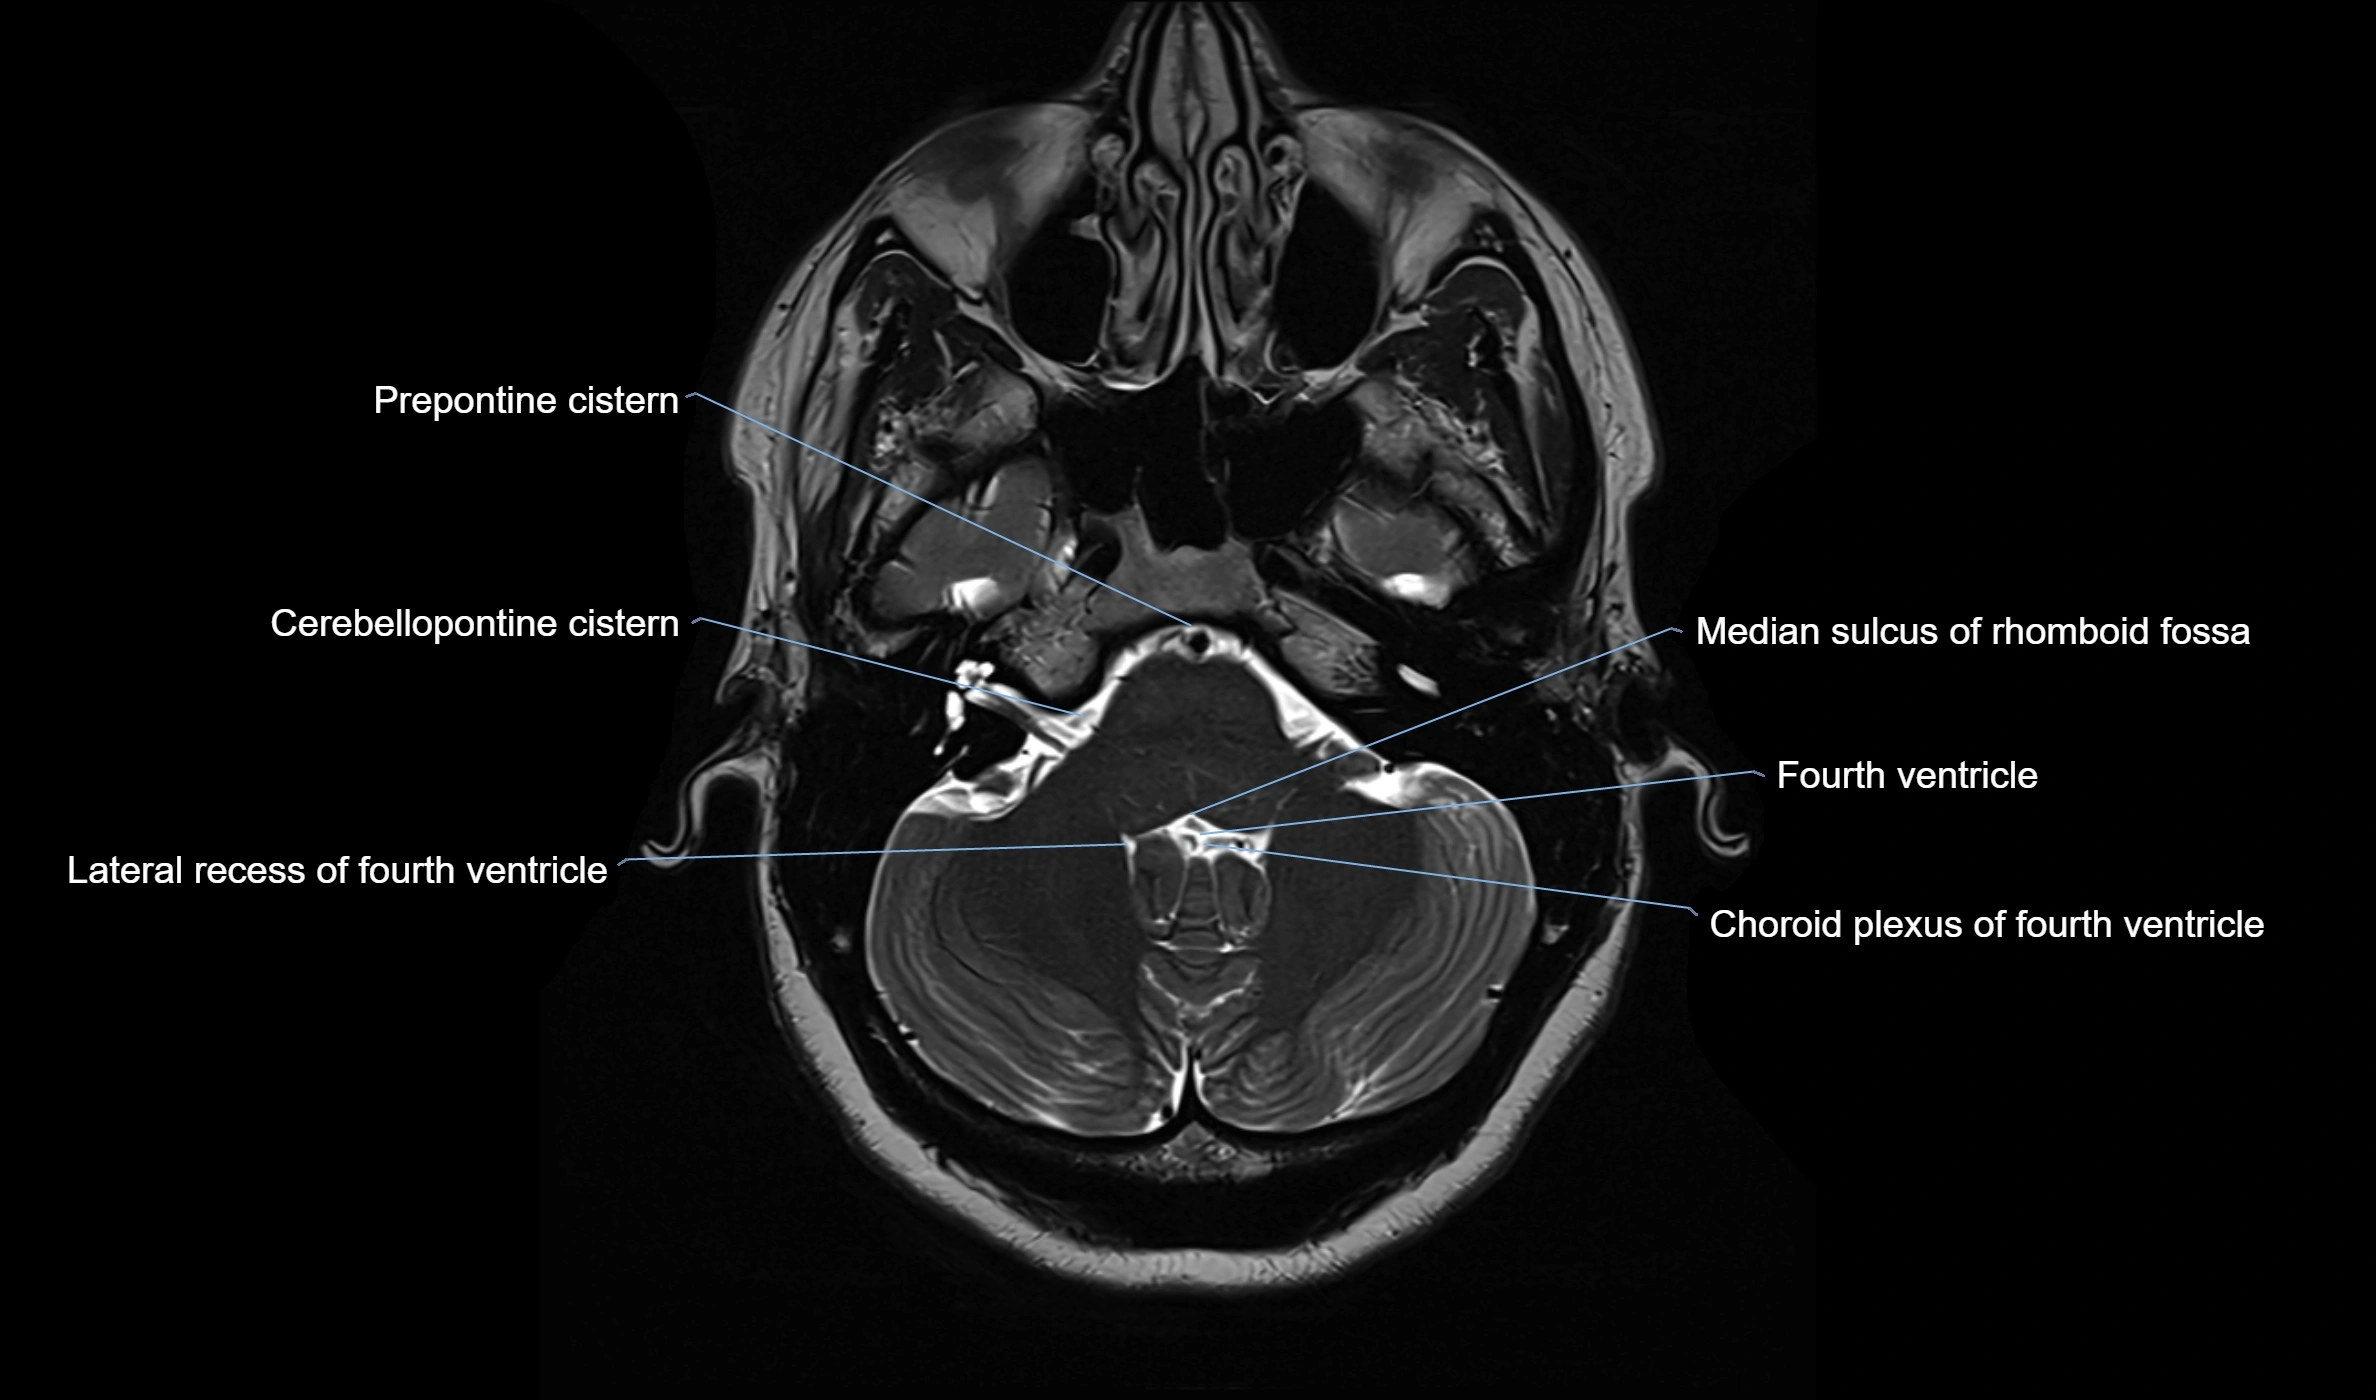

MRI images

image